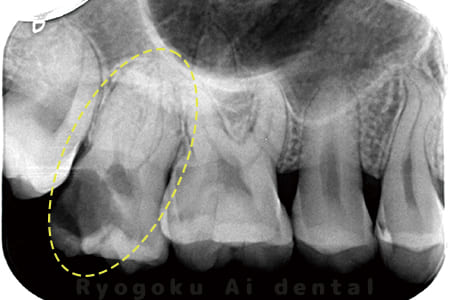

根管内の異物

- 原因

- 根管内異物(ファイル破折)による慢性根尖性歯周炎

- 治療期間

- 3ヶ月

- 治療内容

- マイクロスコープを使用した根管内異物除去並びにマイクロエンド

- 治療費用

- 121,000円(ファイル除去費用も込み)

他院で細い器具(ファイル)が根管内に破折した状態で、咬合痛を主訴に来院された患者様です。ファイルをマイクロスコープ下で除去し、根管治療を行ないました。